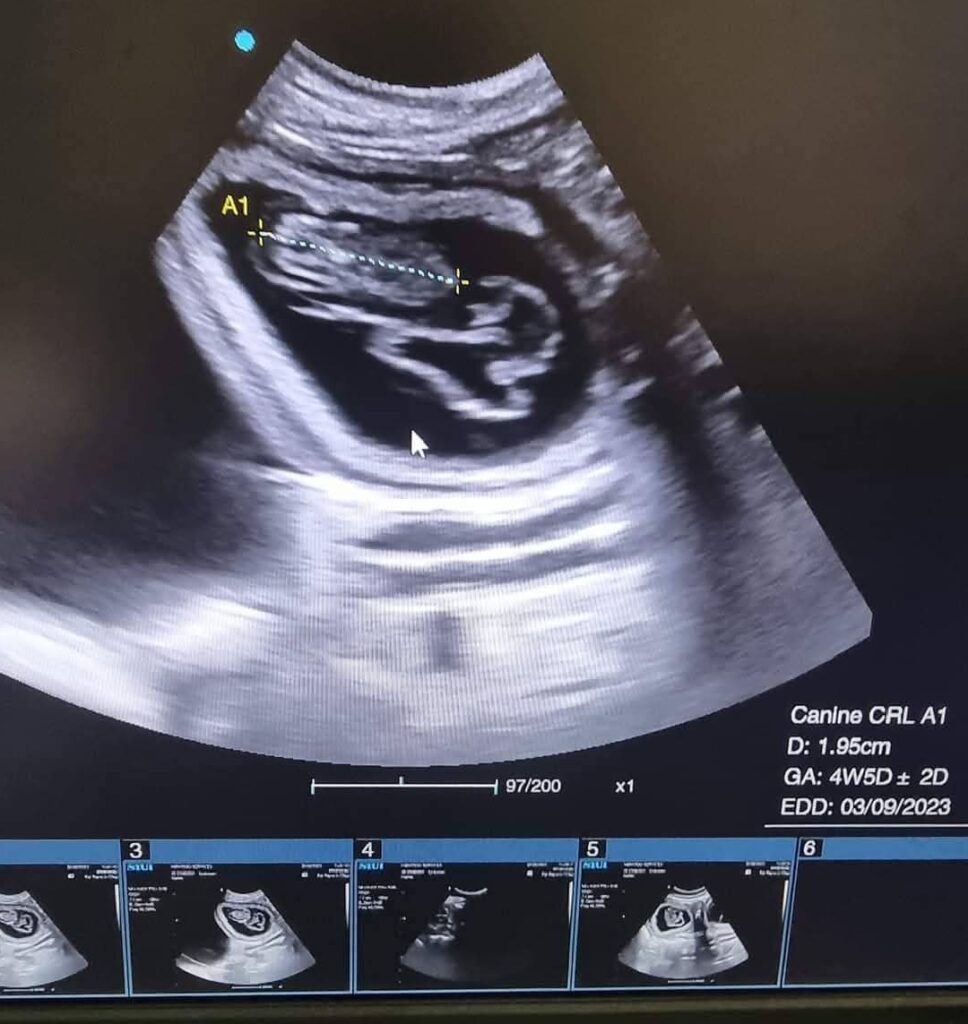

b) Pregnancy Ultrasound

Confirms pregnancy early and monitors fetal development.

6. Can ultrasound detect pregnancy in dogs and cats?

Absolutely. Ultrasound is the most accurate and earliest method to confirm pregnancy in dogs and cats in Kampala. It can also monitor fetal heartbeat, number of fetuses, and overall pregnancy health.

7. How early can pregnancy be seen on ultrasound?

Most dogs and cats can have pregnancy confirmed 2–4 weeks after mating. However, the exact timing depends on the pet, and your veterinarian will advise the best time for the scan.